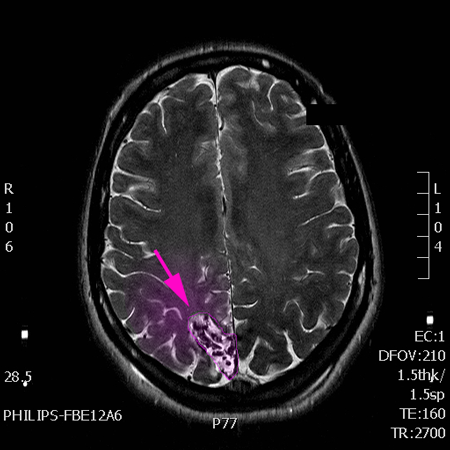

Αρτηριοφλεβώδης δυσπλασία, μάζα παθολογικών αγγείων με χρώμα |